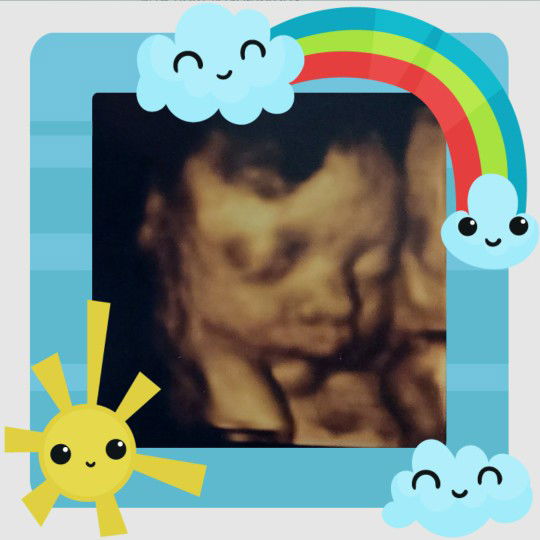

after 2 hours of labor nkaraos din .. Normal Delivery wait ko nlng c baby ko ??